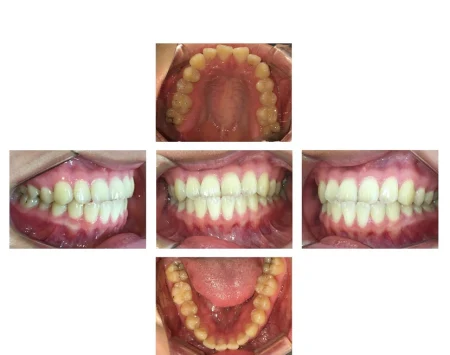

拝見したところ、下の前歯が上の前歯より前に出ている「反対咬合」でした。

反対咬合になっているのは前歯のみで、奥歯の噛み合わせや骨格は問題なかったため、前歯の傾きや位置を調整することで改善できると診断しました。

取り外し式のマウスピース装置「インビザラインGO」で上下の前歯を動かし、歯並びを整える治療をご提案しました。

インビザラインGOを使用して前歯だけを部分的に矯正することで、費用を抑えることができ、治療期間も短くなることを丁寧にご説明し、同意いただきました。

また、前歯の歯並びを整える際に噛み合わせも変わる可能性があったため、それを加味してマウスピースの設計を行い、噛んだ時に歯に負担がかからない歯並びを目指しました。